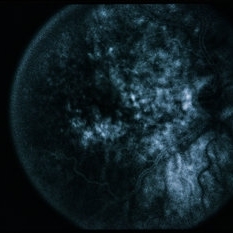

RPE Tear

RPE Tear

Sep 9 2014 by David Callanan, MD

78-year-old male, RPE tear.

Condition/keywords: retinal pigment epithelium